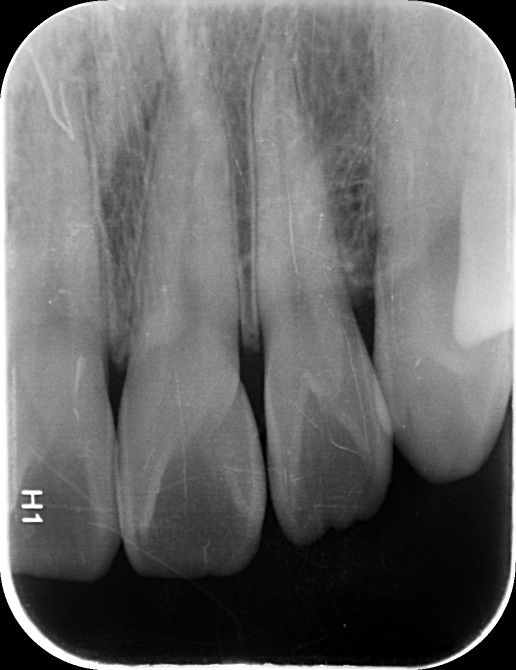

앞니 사이 인접면 충치가 있나요?(사진 첨부)

12, 11, 21, 22 번 4개 앞니 치아들에 대해서

• 3번 째 사진

엑스레이 상으로는 11과 12번의 사이, 21과 22의 사이에 충치가 있는 것으로 보이는데 맞나요?

실제로 바람불어서 긁어봐야 판단이 설 것 같긴한데 일단 엑스레이만 봐서는 관리를 잘한다고 해서 진행을 멈출 사이즈의 충치는 아닌 것 같은데, 지금처럼 인접면 충치의 경우에는 충치부위에 기구접근이 안되기 때문에 딱 충치부분만 제거를 할 수가 없어요. 그래서 좀 더 커질때까지 두고 보자vs지금 치료를 하자 이렇게 나뉜 것 같은데 원래 정석적으로는 바로 치료를 하는게 맞긴 합니다만, 치료를 해서 얻는 것보다 정상치질을 더 제거해야해서 잃는 실이 더 많다고 판단이 되면 좀 더 있다가 하기도 합니다. 이런 애매한 경우는 환자분께서 결정을 하시면 될 것 같습니다.

1. 법랑질 수준에 국한된 충치입니다.

2. 심미적으로 해당 부위가 검게 보이지 않는다면 관리를 하면서 지켜볼 수도 있습니다. 다만 겉으로 보기에는 검게 보인다면 치료를 하는 것이 맞으며 이는 심미적인 이유 때문입니다.

3. 11, 21 모두 치아에 일부 충치가 보입니다. 따라서 2곳 모두 치료해야할 것으로 보입니다.

엑스레이 상으로는 충치가 크게 보이진 않습니다. 저정도라면 저도 일단은 관리를 잘하시면서 지켜보라고 할것같습니다.

사진으로 보기에는 초기 우식이 보이기는 합니다. 하지만 ㅣㅊ료여부는 육안으로 확인을 해야알수가 있어요.

사진응 앞뒤가 겹쳐진 2차원 모잉야지만 충치는 3차원 공간으로 분석을 해야 하기 때문이에요.